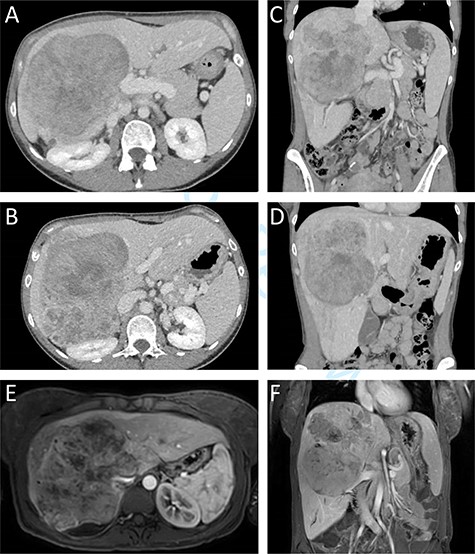

A previously healthy 38-year-old woman presented with a subacute one-month increase of a four-year slowly progressive right sided abdominal and back pain. Ten months prior to her visit she gave birth to a healthy child following an uneventful pregnancy. One month prior to her presentation, blood tests were taken as part of routine evaluation prior to in-vitro fertilization treatments that showed elevated serum hepatocellular enzymes. At the time of her admission an ultrasound was performed revealing an enlarged liver with a non-homogeneous echogenic structure in the right lobe, compressing the portal system. In light of these results and increasing pain she was referred to the emergency department. Upon her arrival her vital signs were normal. Physical examination revealed a large mass, slightly tender to palpation, in the right upper abdominal quadrant. Laboratory blood indices demonstrated a normal blood count, slight elevation of hepatocellular enzymes (ALT = 52, AST = 46) and cholestatic enzymes (GGT = 219, ALP = 435). Bilirubin levels were normal. The CA15.3 tumour marker was elevated (50.1 IU/ml). All other tumour markers including CEA, CA19–9, CA125, and AFP remained within normal limits. Abdominal computed tomography (CT) and magnetic resonance imaging demonstrated a 14.5x12x15cm mass in the right hepatic lobe causing mass effect on adjacent abdominal and retroperitoneal organs, and involving the retrohepatic IVC (Fig. 1). No signs of biliary obstruction were seen.

Preoperative CT and MR imaging. Axial (A + B) and coronal (C + D) CT images depicting a large mass replacing the right liver lobe, involving the retrohepratic IVC and compressing the right kidney. The portal bifurcation is free of tumour and the left portal vein is patent. (E + F) MR images depicting the large lesion occupying the right liver lobe and involving the retrohepatic IVC.